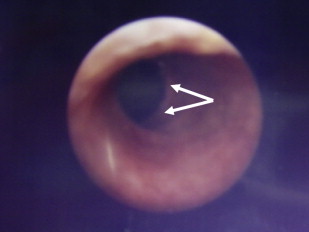

Some forms of epidermolysis bullosa (EB) are particularly susceptible to stenosis or obstruction of the genitourinary tract. Patients typically present with a reduced urinary flow, pain on voiding, or recurrent infections, depending on the site and severity of obstruction. Ulceration and scarring of the glans penis and labia may occur and are a particular feature in the inversa form of dystrophic EB (DEB). Urethral meatal stenosis is also well recognized in both sexes, particularly in patients with recessive DEB and junctional EB (JEB), in whom it has been described in 3% to 4% of patients. In severe cases, this may lead to bladder distension and subsequently hydroureter and hydronephrosis, with chronic renal failure the ultimate consequence if not treated. Partial labial fusion and reflux of urine into the vagina and uterine cavity has been described in one case of DEB. The urethra is also prone to developing strictures ( Fig. 1 ), and these may frequently recur after interventions such as catheterization, urethral dilatation, or electroresection. If instrumentation of the urogenital tract is necessary, it is probably prudent to use the smallest caliber instruments possible to avoid undue damage, or to avoid surgery if at all possible.